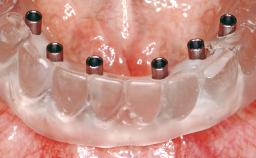

| # of Implants | 8 |

| SAC Level | Complex |

| Defining Characteristics | Fully edentulous upper jaw to be rehabilitated with four or more implants |